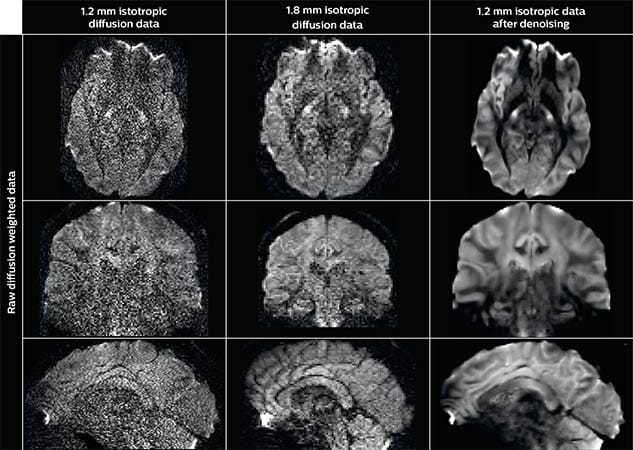

Denoising to improve quality

Using a non-local spatial and angular block matching technique to denoise raw diffusion weighted images. allows to push acquisition to lower spatial resolution and read human-connectome-project-like resolution from standard Philips Ingenia 3.0T MRI scanner. The data were acquired with spatial resolution of 1.2 x 1.2 x 1.2 mm in 13 minutes for 40 full brain DWI with b 1000 and one with b 0